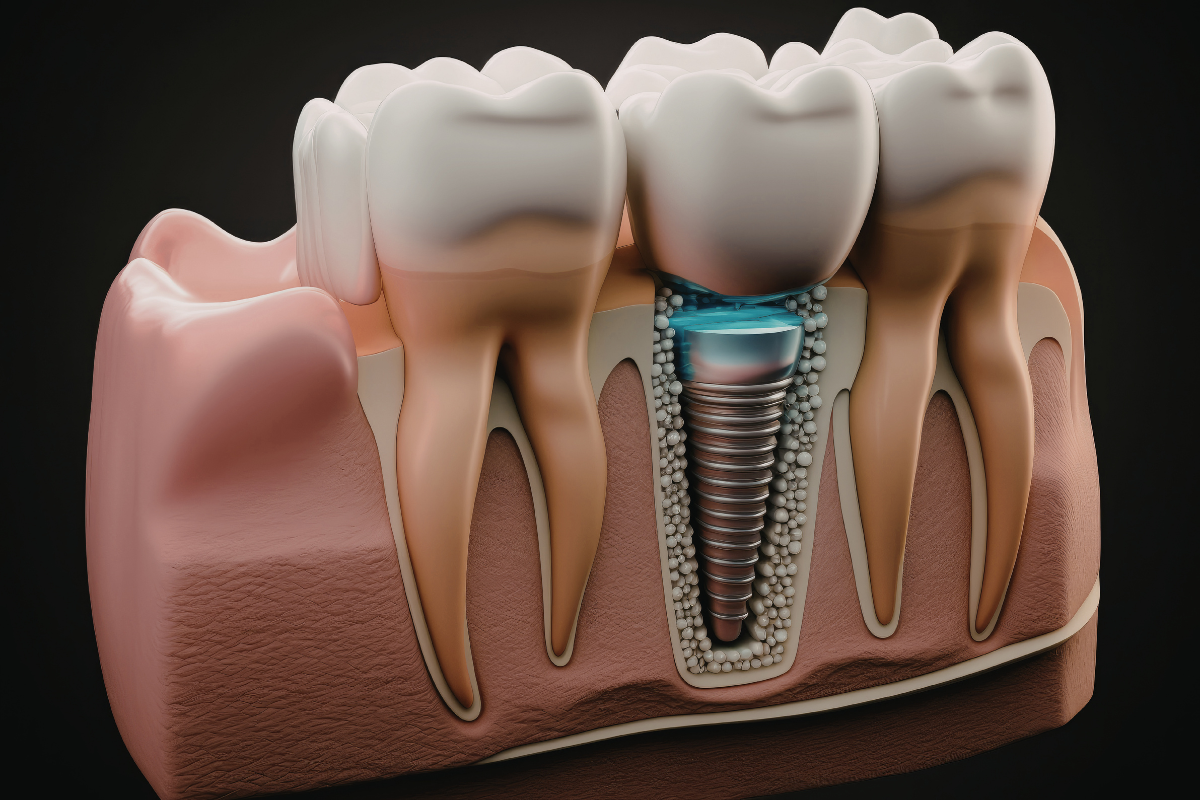

A dental implant is a small titanium post that is placed into the jawbone to act as an artificial tooth root. Once it fuses with the bone, a crown is placed on top to complete the restoration. This makes it a reliable option for Permanent Tooth Replacement in Malad.

Ideal when one tooth is missing. The implant replaces the root and a custom crown blends seamlessly with your natural teeth.

Used when two or more teeth are missing without affecting adjacent healthy teeth.

For patients who have lost most or all of their teeth. This solution restores complete function and confidence.